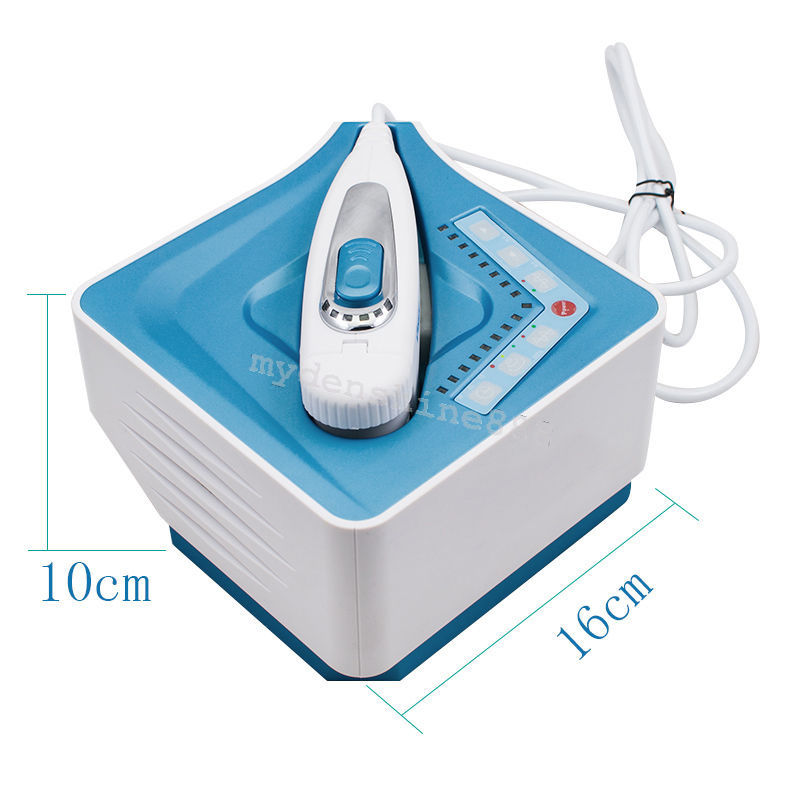

DIAGNOSTIC ULTRASOUND MACHINES FOR SALE

Linear Array Probe D12L40L for Chison Q Series

Sale price$ 6,824.99